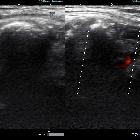

Subclavian

vein aneurysm - Case presentation and discussion. Gray scale and Color Doppler exploration, showing evidence of the patency of the subclavian vein adjacent to the aneurysm.